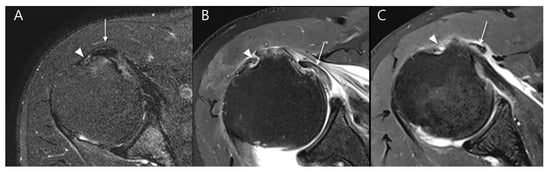

We evaluated the long head of the biceps tendon (LHBT) for various pathologies, including tendinosis, partial tears, complete tears, and instability (subluxation or dislocation) [17]. Tendinosis was defined as an increase in intratendinous signal intensity on T2-weighted images without obvious fiber discontinuity. Partial tears were characterized by focal discontinuity of tendon fibers, whereas complete tears were diagnosed when there was full thickness discontinuity or absence of the tendon in the bicipital groove [18]. Instability of the LHBT, including subluxation and dislocation (Figure 7), was assessed based on abnormal tendon positioning relative to the bicipital groove [19].

Figure 7.

Evaluation of long head of the biceps tendon (LHBT) instability on T2-weighted oblique axial fat-suppressed images in relation to the bicipital groove: (A) LHBT (arrow) is partially displaced to the medial margin of the bicipital groove (arrowhead) without complete dislocation, consistent with subluxation. (B) LHBT (arrow) is completely displaced medially from the bicipital groove (arrowhead) and lies within the glenohumeral joint space, beneath the subscapularis tendon, representing an intra-articular dislocation. (C) LHBT (arrow) is completely displaced medially from the bicipital groove (arrowhead) and is located outside the joint capsule, overlying the subscapularis muscle, representing an extraarticular dislocation.